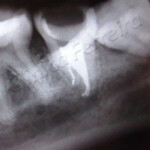

Geralmente, sê num primeiro tratamento, não foi possível seguir os padrões exigidos: limpeza (remoção de todos os microorganismos), preenchimento correto do canal com o material obturador, etc. Essas incorreções podem provocar lesões na ponta da raíz (periápice) do tipo abcessos e lesões crônicas, havendo a necessidade de um novo tratamento, ou seja, um retratamento do dente afetado. Desde que bem executado, este tratamento é eficiente.

Deve-se tomar cuidado, no caso do tratamento do canal não ser realizado, pois poderá se desenvolver uma lesão na região apical (infecção na raíz e nos tecidos vizinhos), que poderá ter conseqüências mais sérias, como dor intensa, inchaço, febre e bacteremia que são bactérias na corrente sangüínea.